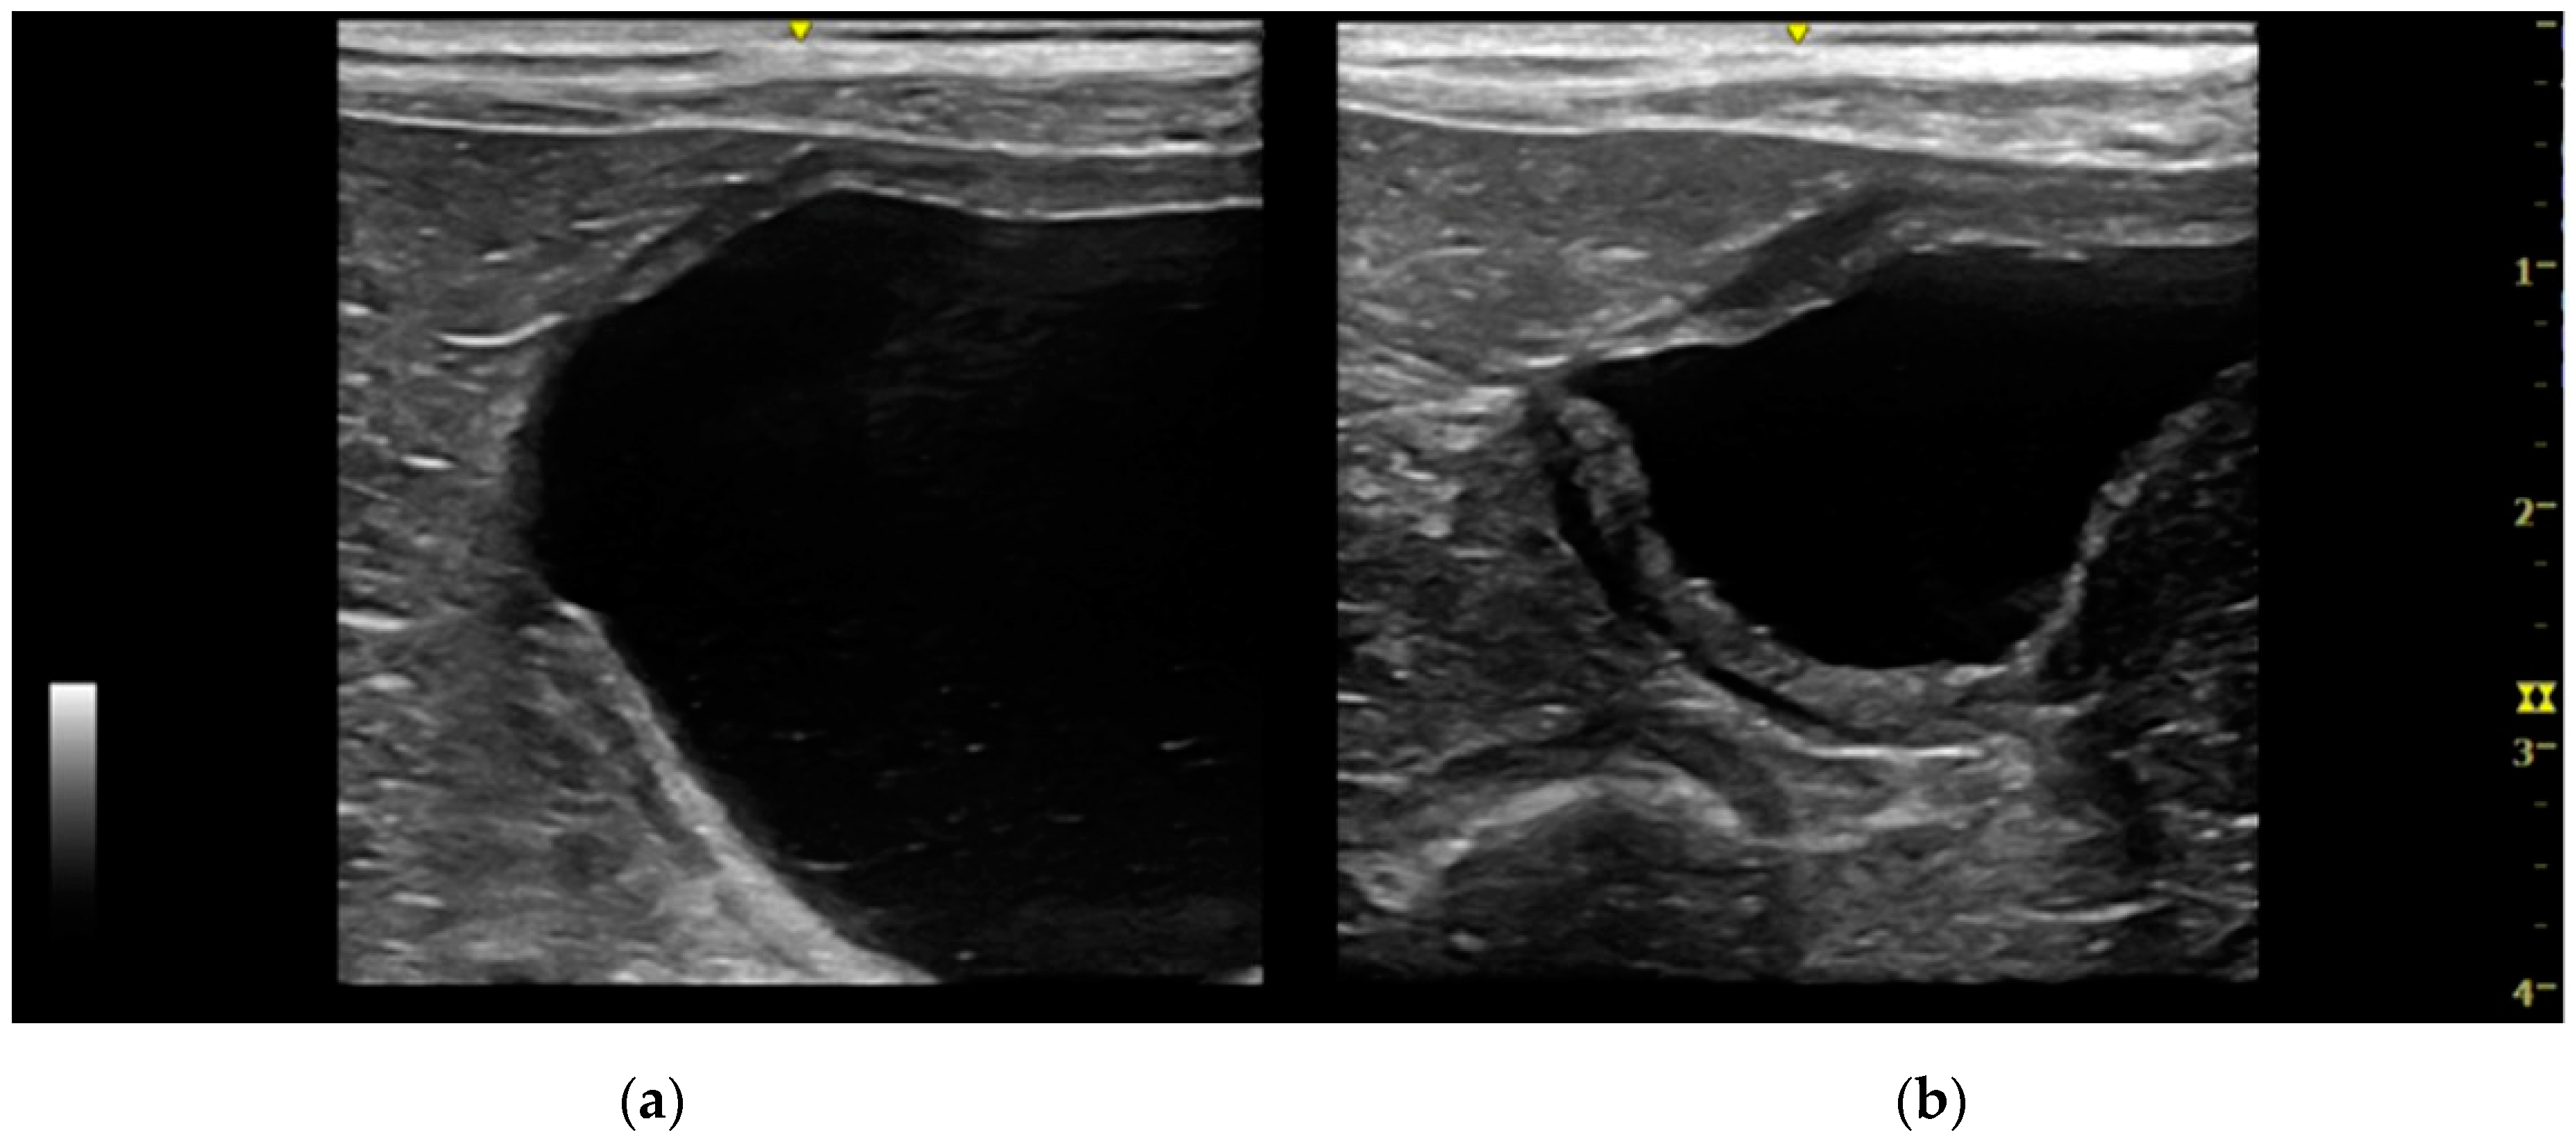

Urachal cyst: only five patients (two cats and three dogs) had this UA. Urachal cysts appeared as round structures in continuity with the bladder wall, with thin and hyperechoic walls and regular margins. It was of different size, from 0.2 to 0.5 cm and the content was always anechoic (Figure 4).

Figure 4. Longitudinal ultrasound image of the cranioventral part of the urinary bladder in a cat, showing the presence of a small (<1 cm diameter), well-defined, round, thin-walled, anechoic formation, cranial to the bladder apex, consistent with urachal cyst. The urinary bladder is empty.